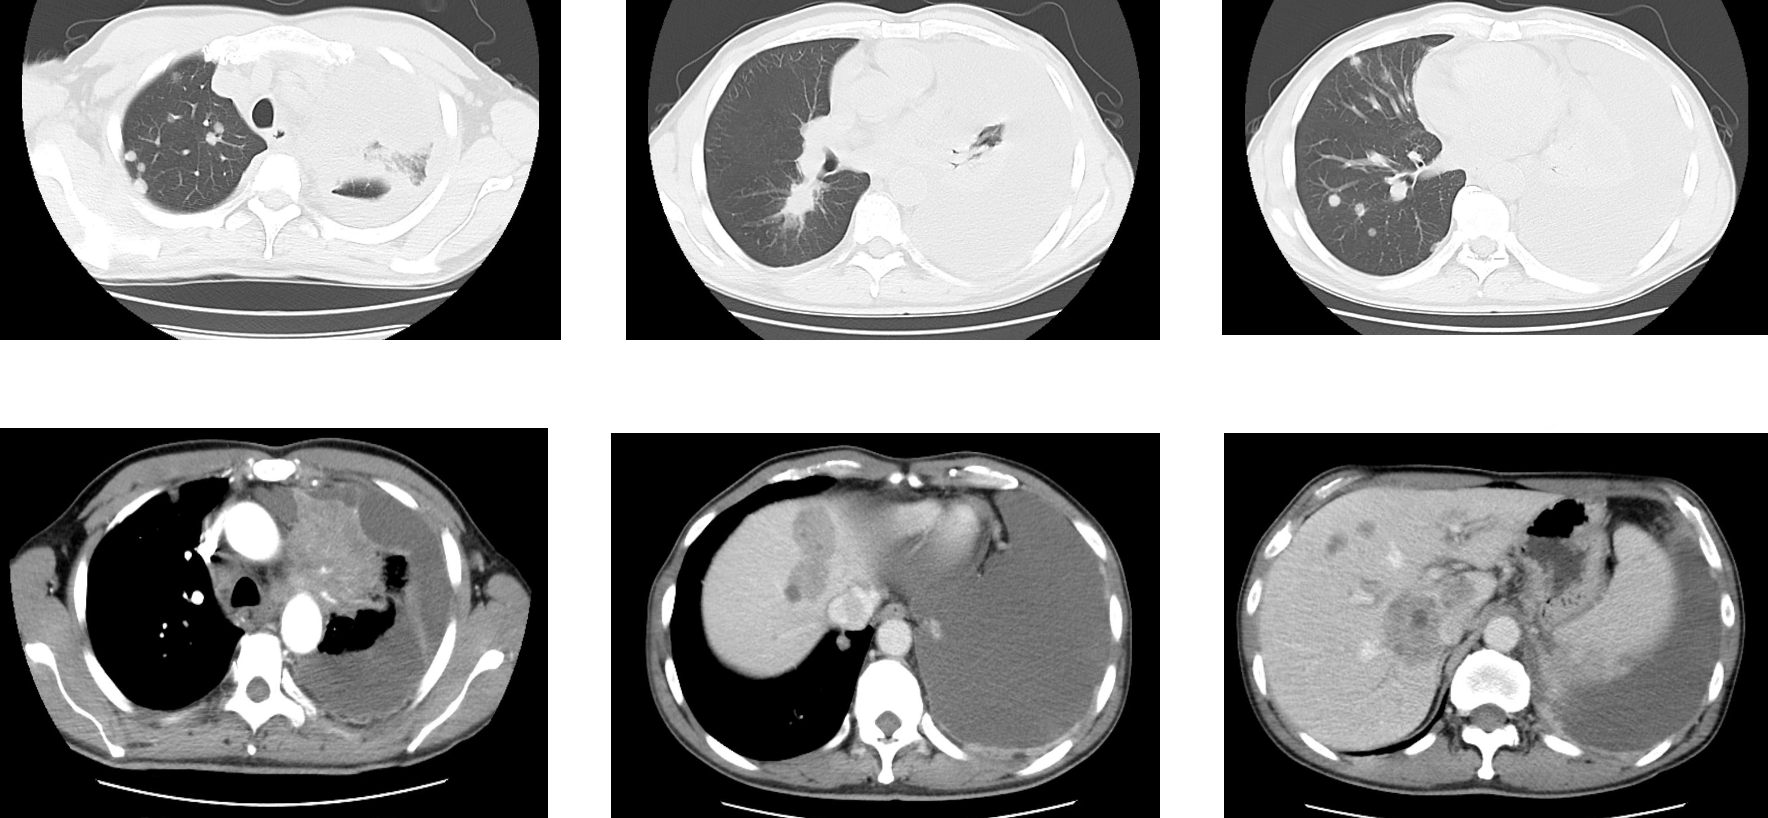

艾托组合抗体治疗:2024年10月至今

患者采用艾托组合抗体(PD-1/CTLA-4组合抗体)联合卡铂和安罗替尼治疗,同时进行血管内皮抑素胸腔灌注控制胸水。第一周期治疗后出现发热气喘等不良反应,经对症处理后症状改善。6周期治疗后影像学评估显示肺部病灶明显缩小,肝脏及淋巴结转移灶缩小,胸腔积液减少,疗效评价为PR(部分缓解),患者临床症状明显改善,生活质量显著提升。

1. 艾托组合抗体联合方案治疗6周期后,患者肺部病灶明显缩小,肝脏及淋巴结转移灶缩小,胸腔积液减少,疗效评价为PR(部分缓解);